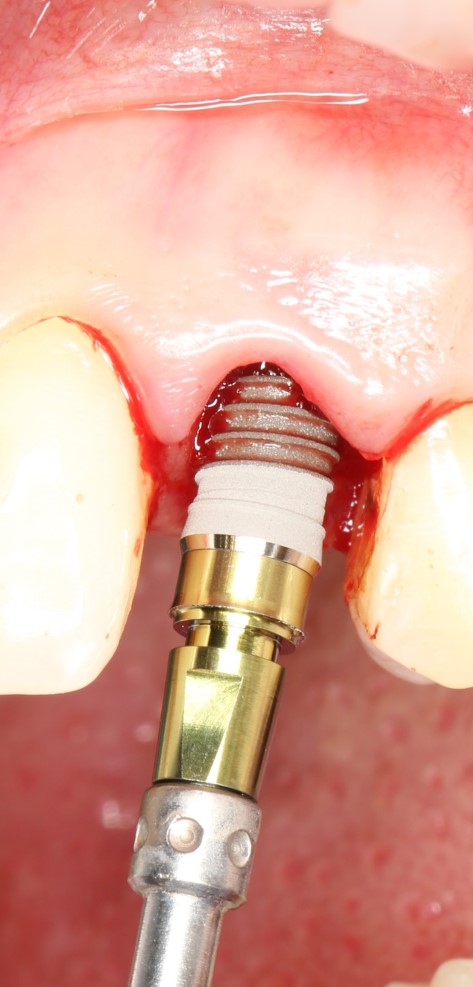

Затем уложили ксенографт. Особенностями Bio-Oss Collagen являются удобство адаптации, устойчивость к вымыванию и выдавливанию, поэтому мы просто уложили полученные ранее пирамидки вестибулярно относительно будущего имплантата, после чего прижали их с помощью уже упоминавшихся аналогов имплантата, входящих в хирургический набор имплантационной системы Xive (кстати, при работе с другими имплантационными системами для паковки графта в лунке можно использовать круглые остеотомы для синуслифтинга).

В совокупности, аугментация лунок перед установкой имплантатов занимает около 20 минут — и это самый долгий из всех хирургических этапов лечения.